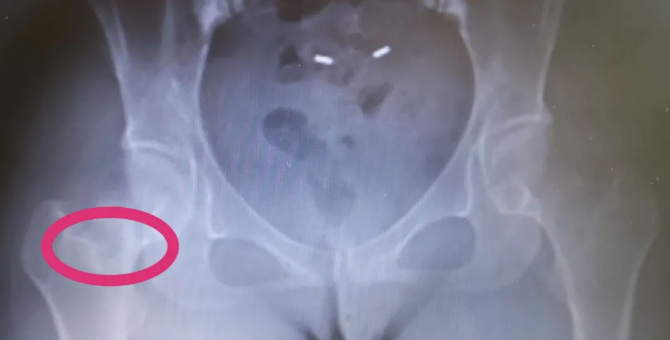

4个月前,顾女士的右侧髋关节出现隐隐作痛的感觉,但关节活动非常好,也没有活动障碍的感觉,一直没到医院正规诊治 。但由于隐痛频繁发生,不久前,她来到即墨人民医院骨外一科就诊 。X线片检查示:右股骨颈有骨质破坏表现 。进一步CT检查,考虑骨纤维异常增殖症 。由于瘤体非常大,股骨颈骨质破坏已经非常严重,极易出现股骨颈骨折 。顾女士听取医生建议,住到骨外一科病房 。

【|即墨一女子右腿隐痛 竟然是骨头在自身吸收】手术顺利进行,医生在顾女士的股骨颈前方正中位置开了一个1.5×0.5cm骨窗,尽量在能够彻底切除病灶的前提下减少对股骨颈的破坏 。在彻底清除病灶后,给予取同侧髂骨植骨填充股骨颈的空缺,并给予动力髋接骨板(DHS)支充 。病人术后就可以不负重活动髋关节,第二天切口疼痛明显减轻,并可扶双拐下地活动 。出院时髋关节的隐痛感已完全消失,及时手术避免了她因为股骨颈骨折而失去髋关节的人生遗憾 。